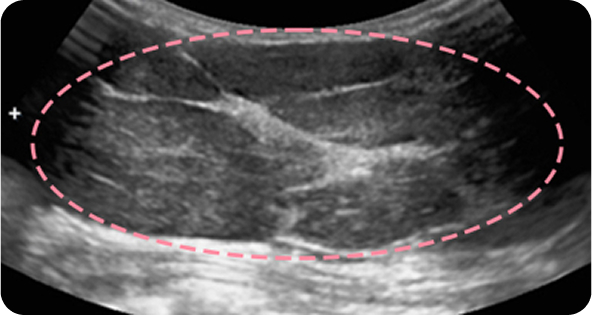

양성 종양은 여러 개가 동시에 생겨나기도 합니다. 정상적인 유방 조직 보전에 신경 쓰며 맘모톰 시술을 섬세히 진행했고, 6개월 뒤 추적 관찰을 위한 유방초음파에서 종양이 깨끗이 제거된 것을 확인했습니다. 일부 반흔 조직은 자연스럽게 호전될 것으로 보여 좋은 예후가 기대되었습니다.